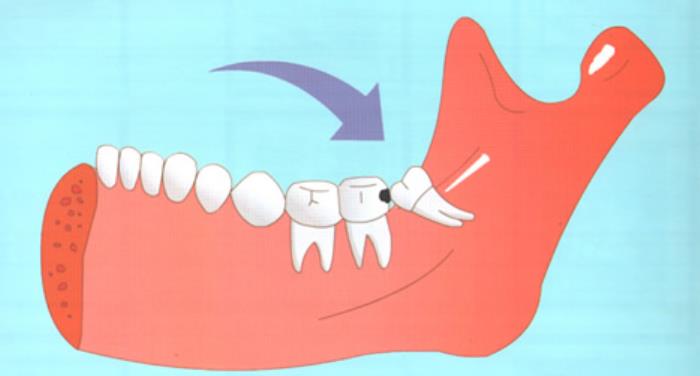

长歪的智齿常常会排挤前牙,甚至会顶坏前牙牙根。智齿不易清洁,牙周卫生不好的话,所以爆发龋齿、牙周病几率很高,还会连累前牙。